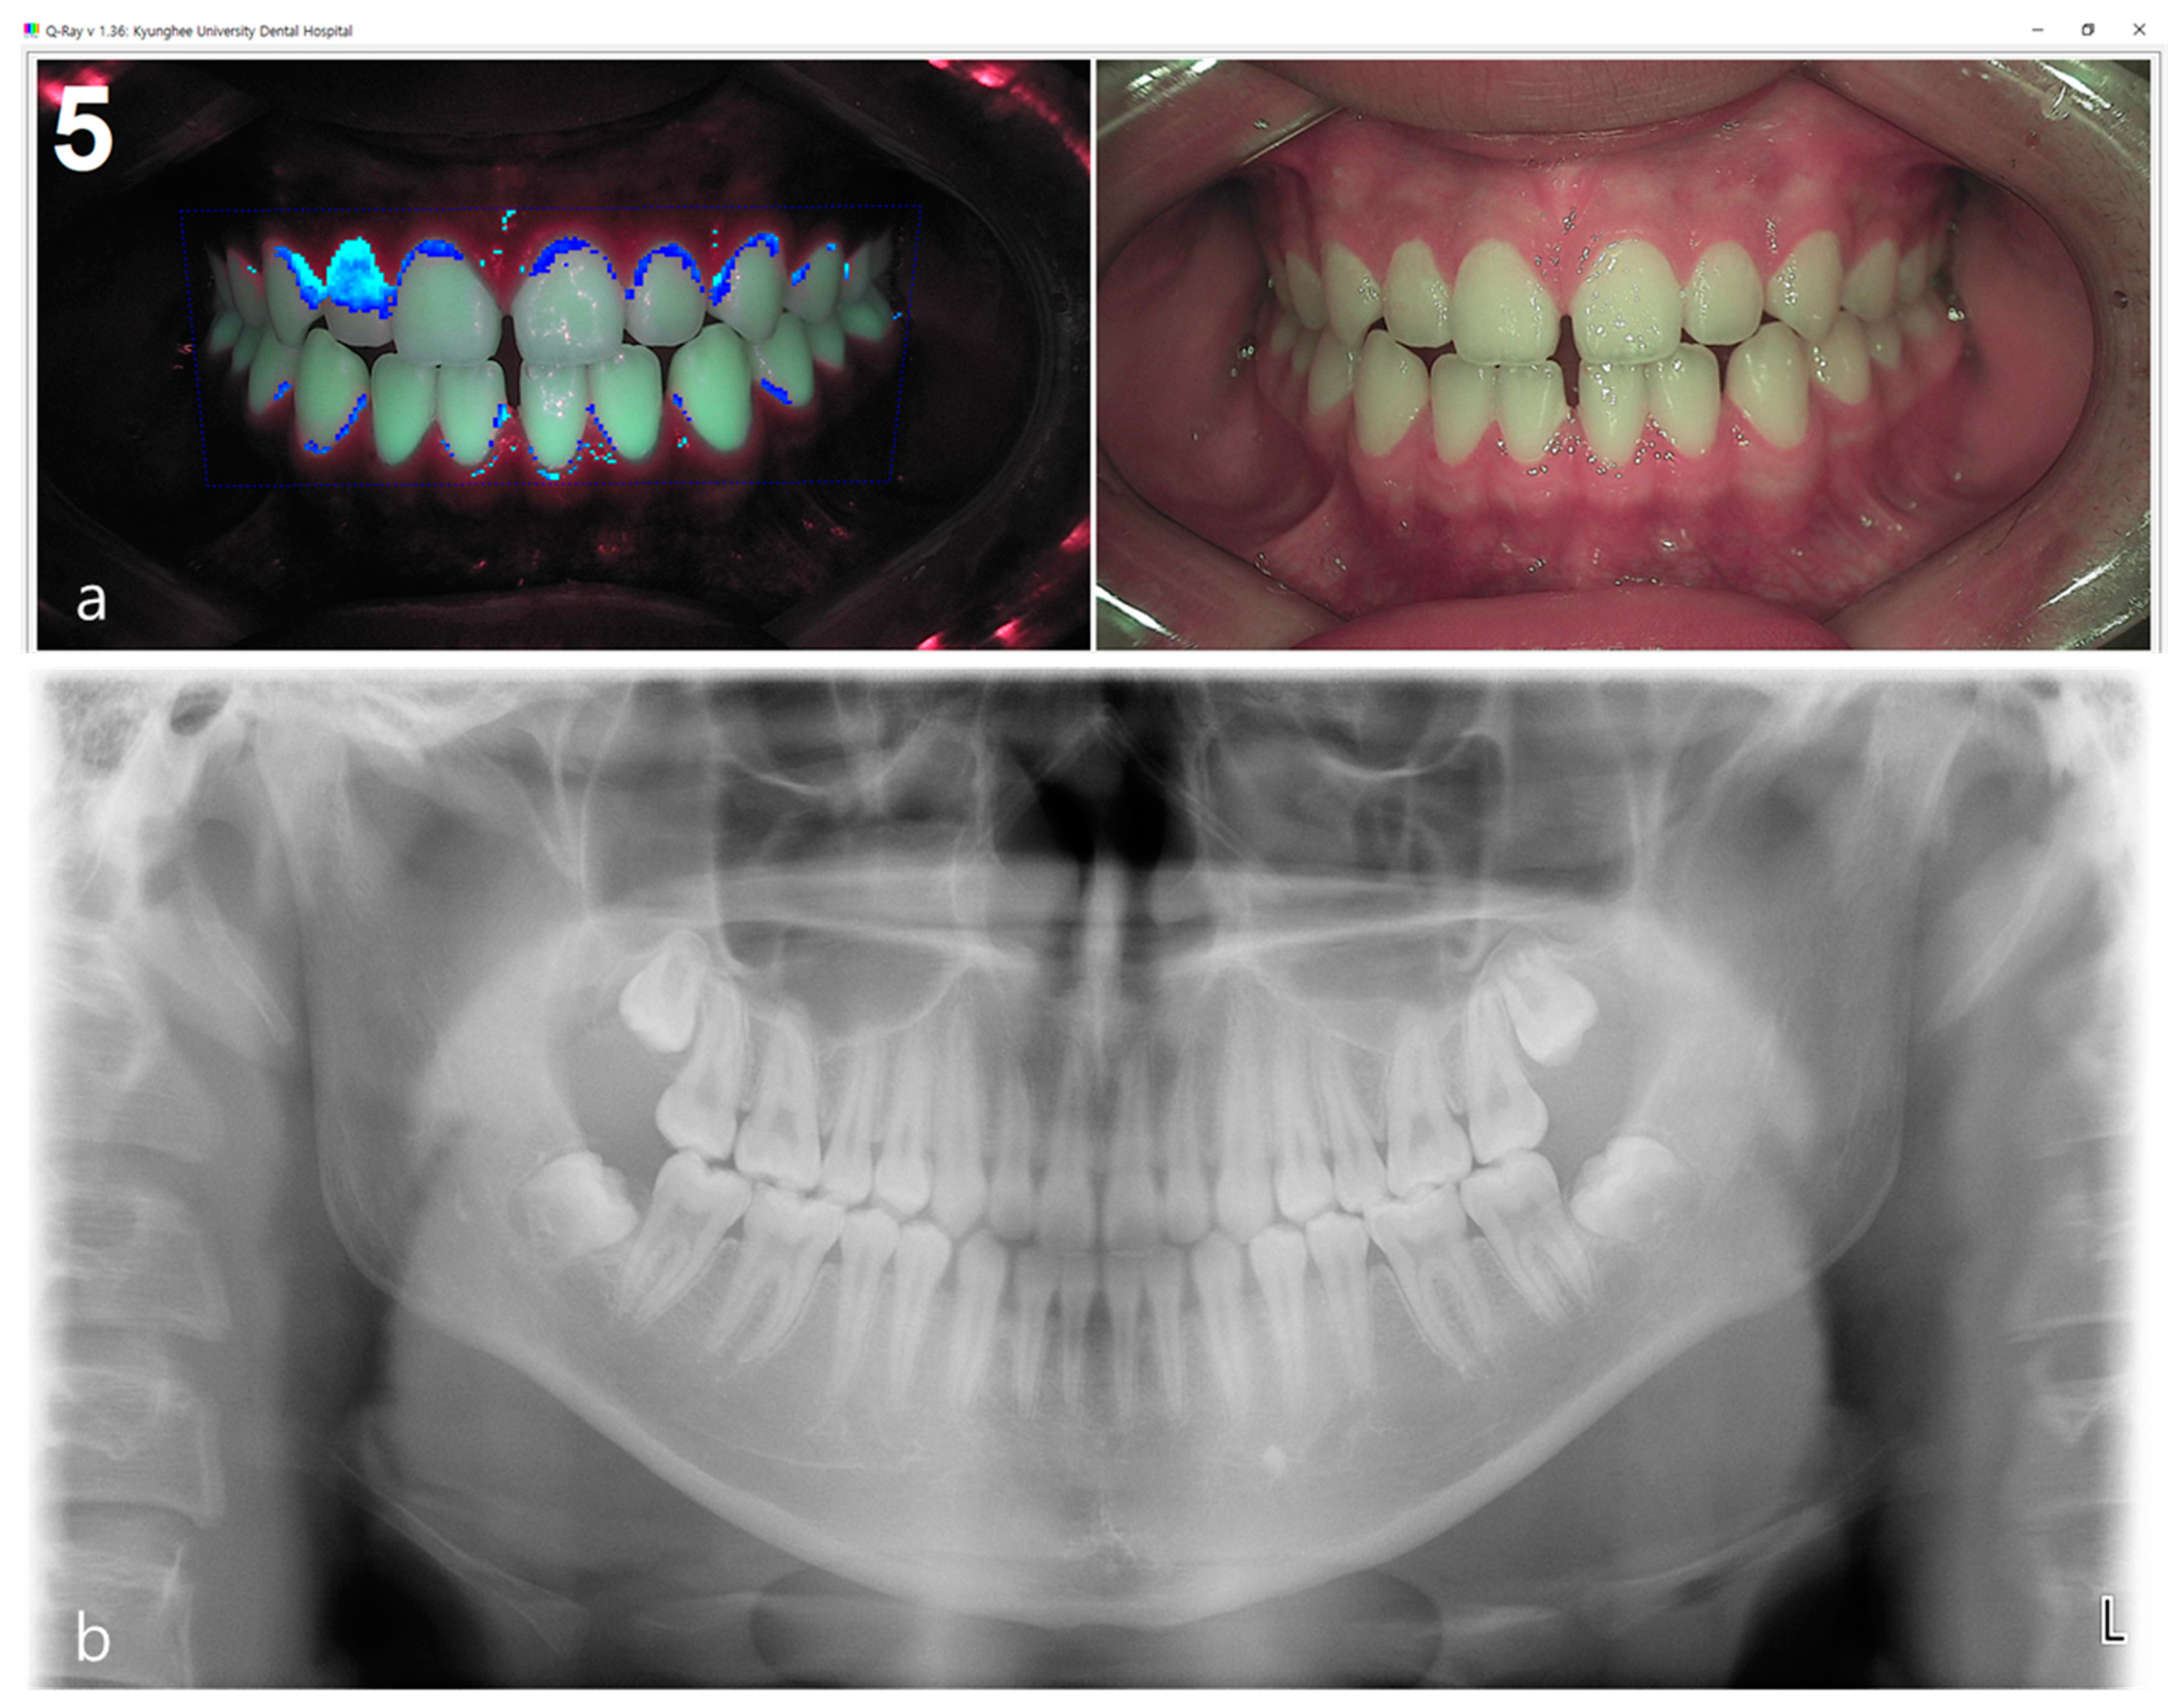

Figure 1.

(a) Fluorescent plaque index (FPI) score using propriety software of the quantitative light-induced fluorescence (QLF) system was 5 which shows a serious degree of dental plaque pathogenicity, (b) while the score of radiographic bone loss (RBL) shown in the panoramic image was 1.1 which was close to normal.